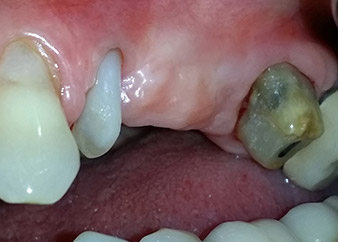

apikale Parodontalläsion an Zahn 24

Abb. 1: Bei einer 58-jährigen Patientin zeigt die Röntgenaufnahme vor der OP eine apikale Parodontalläsion an Zahn 24 und einen horizontalen Knochenabbau im zweiten Quadranten.

Eine 58-jährige Patientin, die auch eine gute Freundin und ärztliche Kollegin ist, beschwerte sich über Schmerzen und erhöhte Beweglichkeit ihres Brückenpfeilers 24. Es lag auch eine parodontale Entzündung vor, mit Taschentiefen von 7 mm mesiobukkal und mehr als 12 mm distal und einer Furkationsbeteiligung dritten Grades. Darüber hinaus zeigte die Röntgenaufnahme eine großflächige apikale Aufhellung am endodontisch (alio loco) vorbehandelten Zahn 24 (Abb. 1).

Ein Jahr zuvor waren die Zähne 25 und 26 vor dem Einsetzen der Brücke aufgrund traumatischer und endoparodontaler Ursachen extrahiert worden. Eine Paro-Endo-Läsion wurde bei unklarer ätiologischer Hauptkomponente für den Zahn 24 diagnostiziert. Die Patientin machte deutlich, dass sie ihre Pfeilerzähne 24 und 27 behalten und keinen endgültigen oder temporären herausnehmbaren Zahnersatz akzeptieren will. Darum wurde vereinbart, alles zu versuchen, beide Zähne, trotz der nach den radiologischen und klinischen Befunden als schlecht einzustufenden Prognose, zu erhalten.